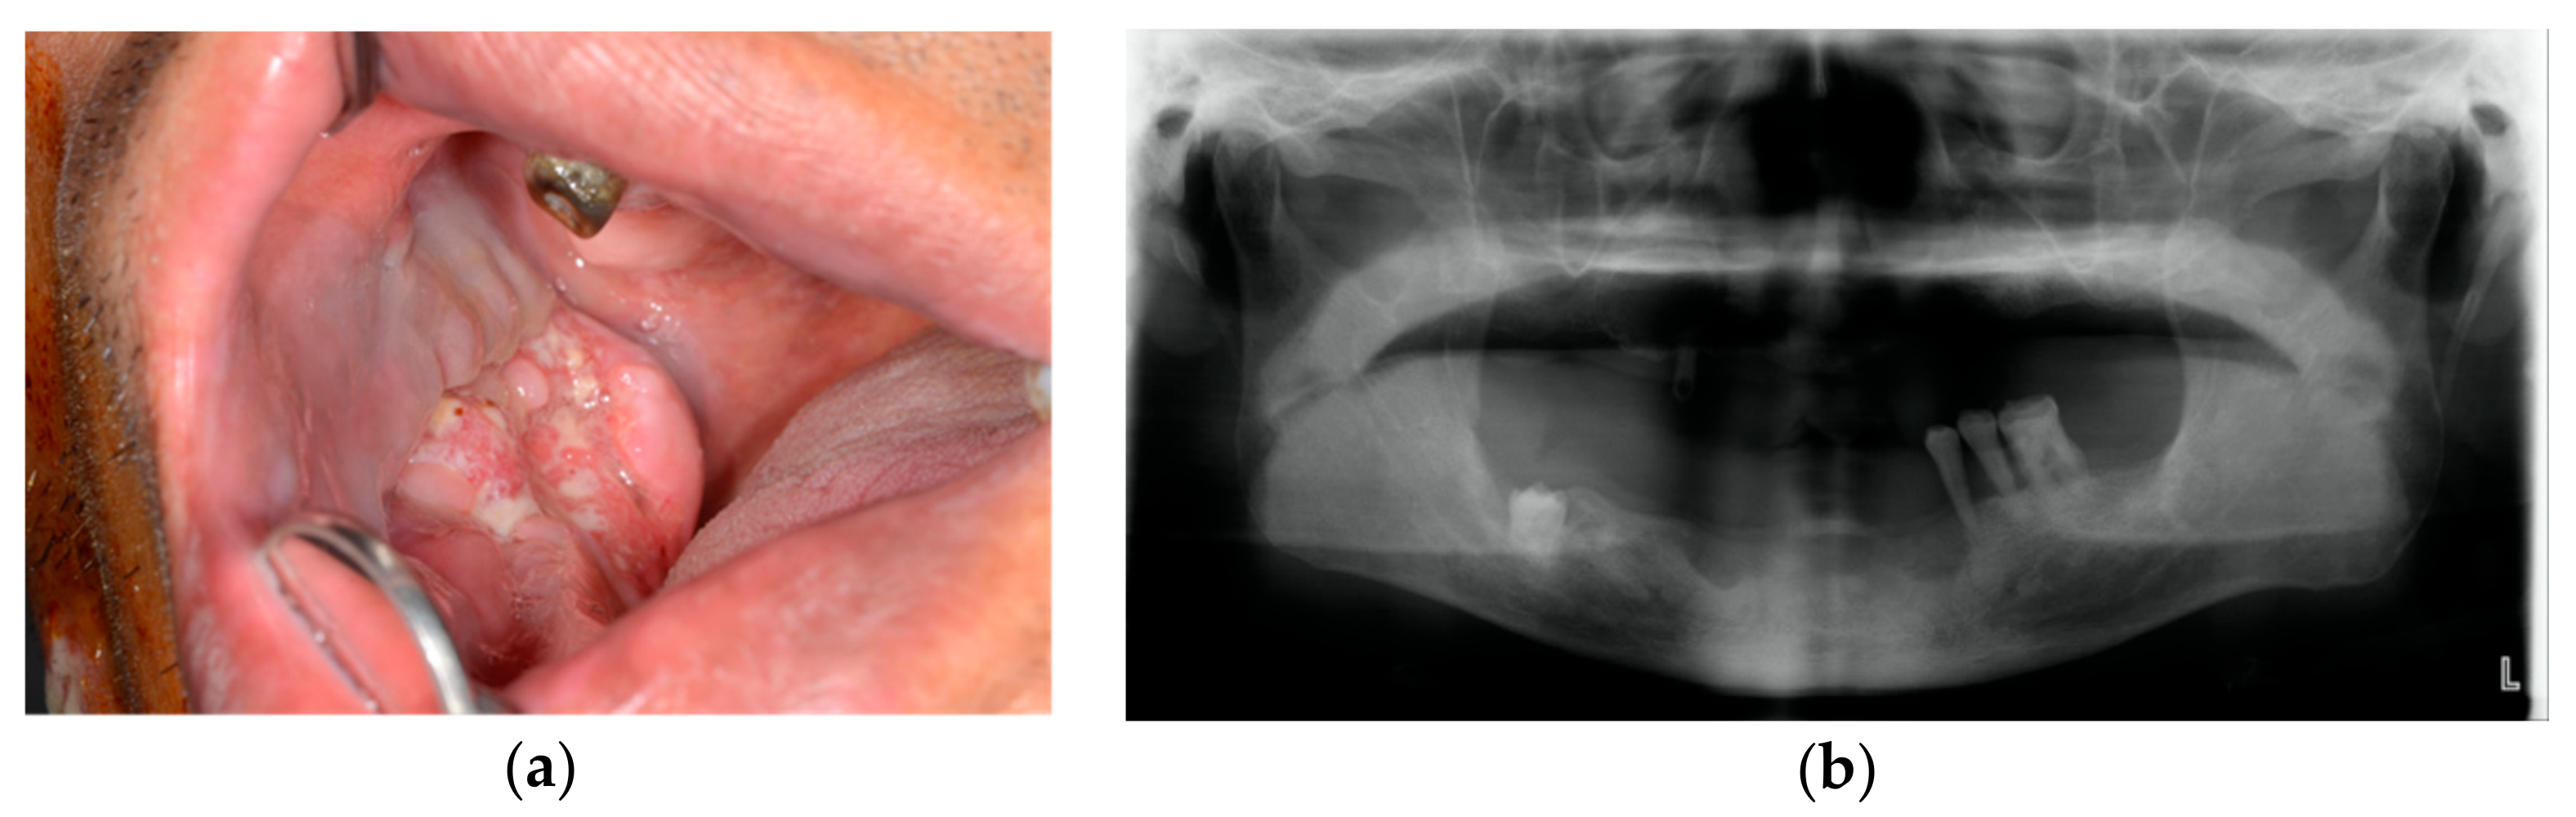

2. Case Presentation